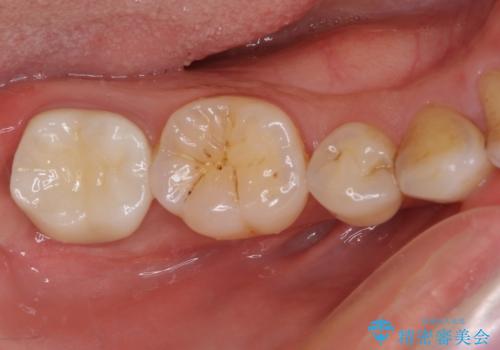

根管治療後の補綴治療 奥歯のセラミッククラウン

- 根管治療の専門医院で根管治療を行った後、セラミッククラウンによる補綴治療を希望して来院された患者様です。

根管治療後の土台も構築されていたので、仮歯に置き換えた後にフルジルコニアクラウンにて補綴することとしました。

遠心の歯肉が盛り上がっていたため、清掃性が悪くなる懸念がありましたが、クラウン装着による歯肉の腫れは認められませんでした。